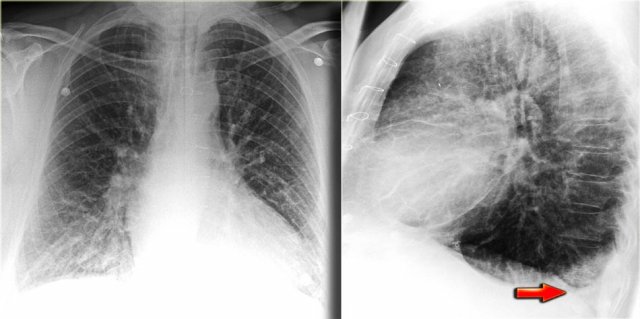

Pleural effusion more evident on lateral view Pleural effusion more evident on lateral view

Pleural effusion is bilateral in 70% of cases of CHF.

When unilateral, it is slightly more often on the right side than on the left side.

There has to be at least 175 ml of pleural fluid, before it will be visible on a PA image as a meniscus in the costophrenic angle.

On a lateral image effusion of > 75 ml can be visible.

If pleural effusion is seen on a supine chest film, it means that there is at least 500 ml present.

On the left images of a patient who has bilateral pleural effusions.

Notice that it is more evident on the lateral view.